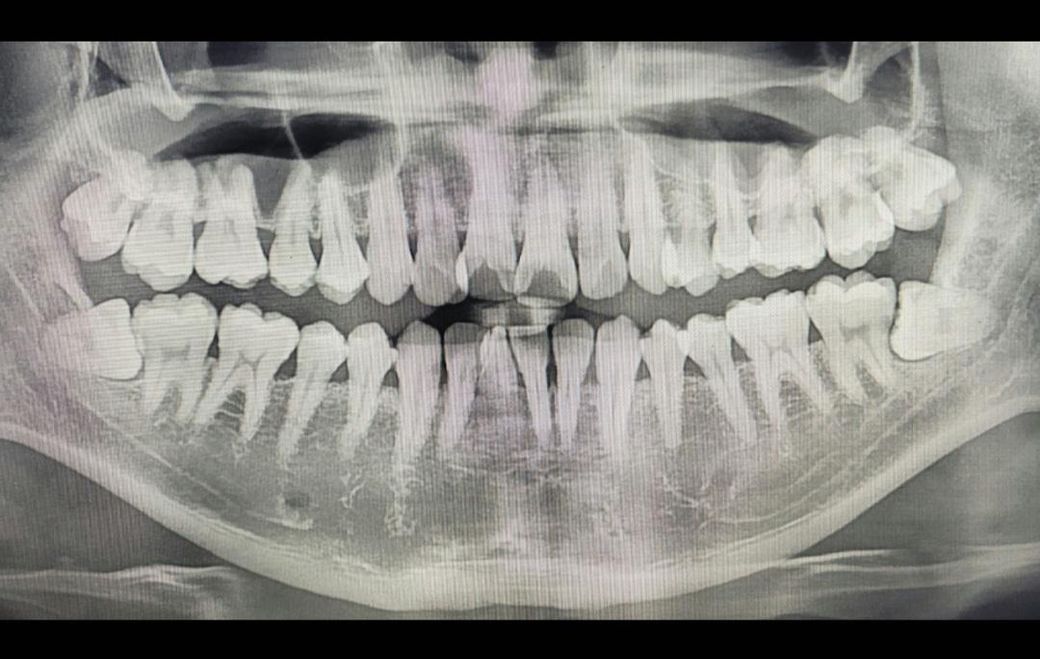

왼쪽 (사진상으론 오른쪽) 사랑니 바로 아래 어금니 통증이 깨물때 살짝 있길래

• 1번 째 사진